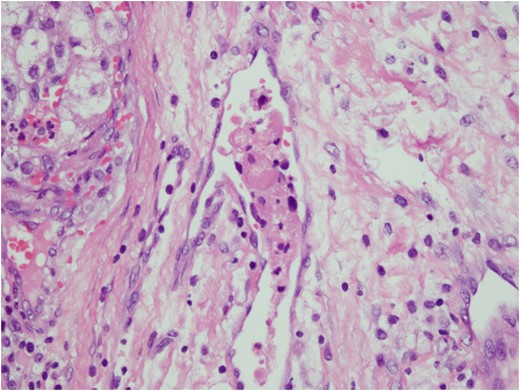

Histologic sections of the mass show distinct variably sized and shaped collections of uniform polygonal tumor cells, separated by fibrovascular septa and delicate capillary-sized vascular channels lined by flattened endothelium at low magnification (Fig. 5). Within the tumor nests, there is loss of cellular cohesion and necrosis of the centrally located cells in the nests results in the pseudo-alveolar pattern (Fig. 6). Vascular invasion is also present (Fig. 7). The individual tumor cells have distinct cell borders and abundant eosinophilic to clear, somewhat granular cytoplasm surrounding a central nucleus with variably sized nucleolus. Nuclear atypia is rarely seen. Mitotic figures are uncommon. The cells contain rhomboid or rod-shaped crystalline inclusions that are faintly apparent on routine histology and are better demonstrated with periodic acid-Schiff stain after diastase digestion (Fig. 8).

Loss of cellular cohesion and necrosis of the centrally located cells in the nests.